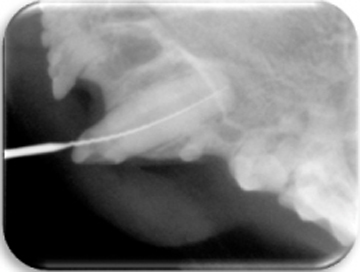

El diagnóstico clínico oral es de suma importancia ya que el plan de tratamiento y el pronóstico dependen de un certero y profundo análisis de los signos de la cavidad oral. Nuestra principal preocupación es atender los problemas que se encuentran en cavidad oral pero además siempre realizamos un detallado análisis de la función general del paciente. En nuestro centro revisamos de manera general a la mascota detectando cualquier problema sistémico. Contamos con un laboratorio de análisis clínicos en donde se realizan biometría hemática, química sanguínea, examen general de orina y pruebas para detección de enfermedades virales y de otros microorganismos. Contamos también con un laboratorio de histopatología en donde se revisa el material biológico para la detección y el diagnóstico de cambios morfológicos y lesiones en los tejidos. En lo que respecta al diagnóstico de la boca, contamos con un expediente donde se vacía toda la información dental y bucal de tal manera que mantenemos el control del tratamiento odontológico desde el inicio hasta el final y en donde el propietario o el médico que nos recomienda puede revisar en detalle toda la información recabada. Contamos con todo el instrumental y el equipo necesario para el diagnóstico de el aparato estomatognático (cavidad oral con dientes, tejidos de sostén y tejidos blandos, además de las estructuras relacionadas como articulación temporomandibular, cavidad nasal, cavidad orbitaria, etc.). Contamos con luz similar a la ultravioleta para diagnóstico de lesiones dentales por transluminación, pulpómetro para diagnóstico de vitalidad pulpar, localizador de ápices para tratamiento de conductos y equipo radiográfico tanto analógico como digital.